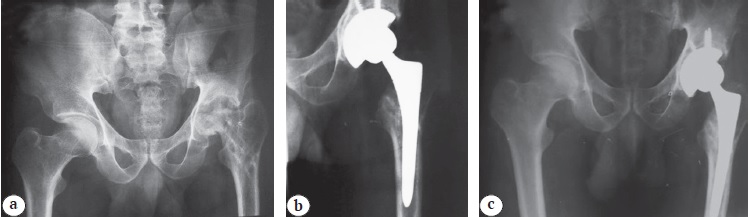

Figure 3. A 30-year-old male patient with advanced left hip avascular necrosis with failed previous core decompression and collapsed femoral head, cementless THA (metal-on-polyethylene bearing surface): a — preoperative X-rays; b — X-rays at 6 months post-operatively; c — X-rays at 20 months post-operatively